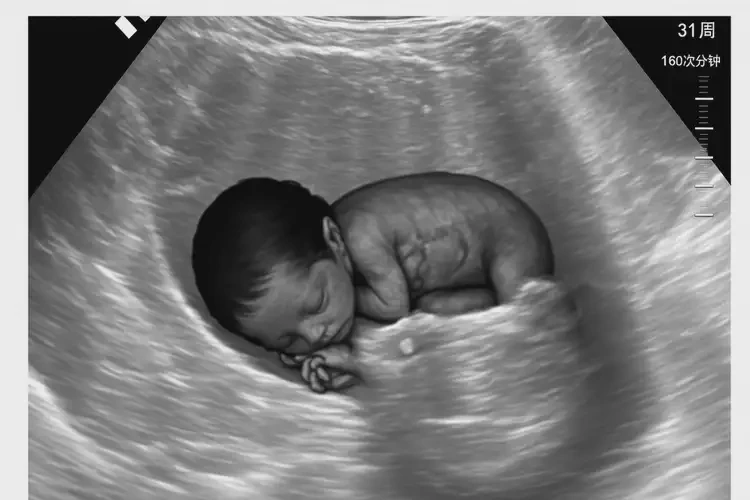

孕31周3天胎心率160有危險(xiǎn)嗎

160次/分鐘

孕31周3天的胎心率在160次/分鐘,通常屬于正常范圍。胎兒的正常心率范圍是120-160次/分鐘,因此160次/分鐘并未超出正常上限。胎心率的解讀需要結(jié)合具體情況,包括孕婦的身體狀況、胎兒的活動(dòng)情況以及監(jiān)測(cè)時(shí)的背景環(huán)境等。

孕31周3天胎心率160有危險(xiǎn)嗎(圖1)